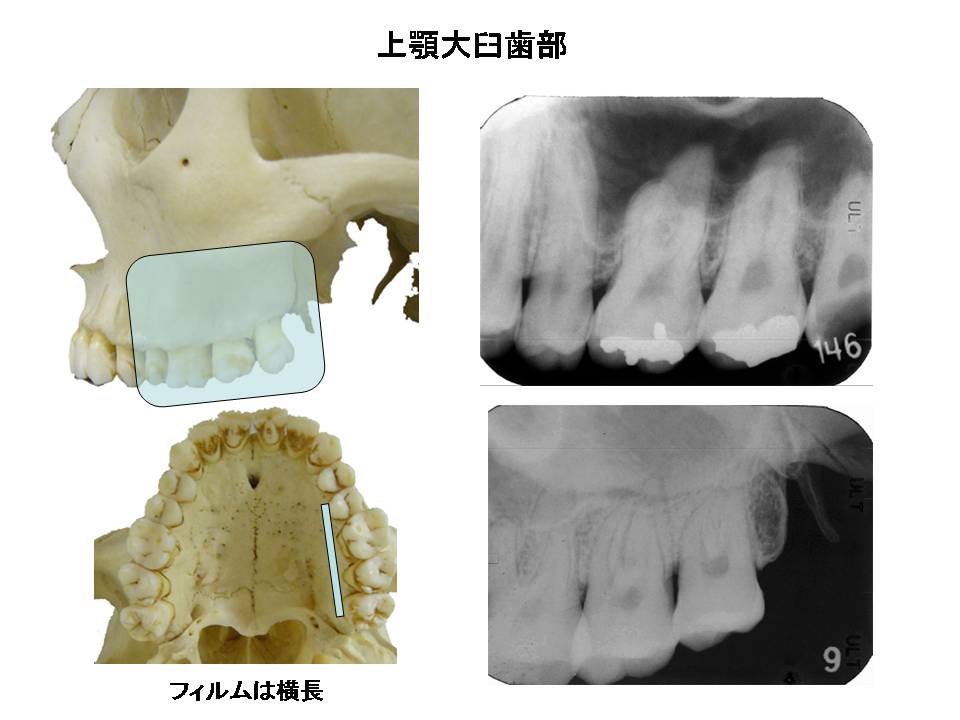

口内法(二等分法・咬合法)撮影の解剖